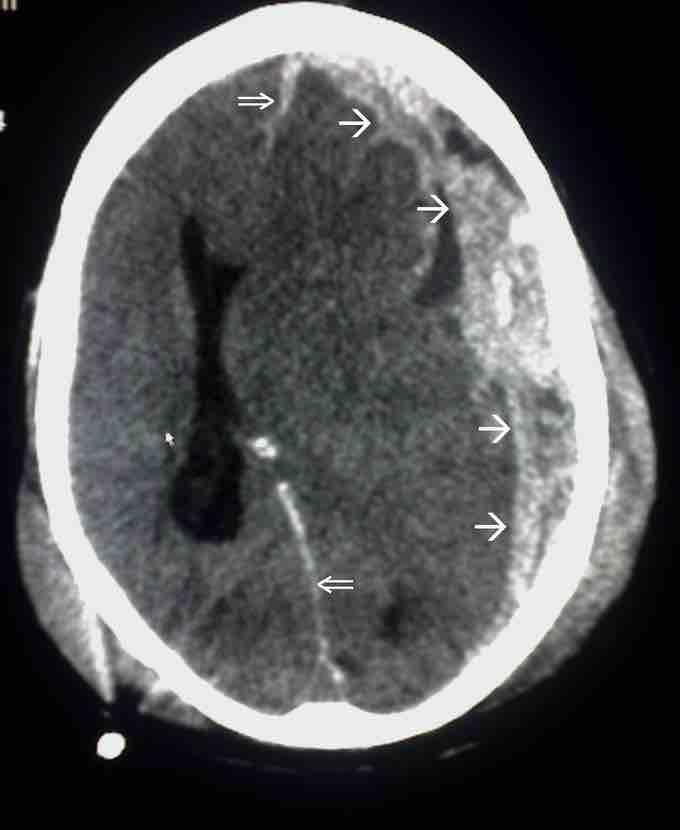

Subdural hematoma is a possible result of traumatic head injury

In this image, the single arrow marks spread of the subdural haematoma and the double arrow marks the midline shift.